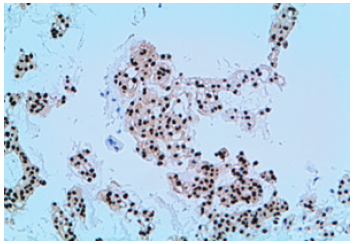

Figure 4:On immunochemistry Anti-Pancitocheratin antibody (AE1/AE3), S100, EMA, and vimentin were intensely and diffusely positive; anti-CDX2 antibody showed a weak/focal positivity (10x).

Histological specimens obtained from endoscopic biopsies showed clusters of medium/large-sized epithelioid cells, with abundant clear cytoplasm and round nuclei, suggestive of a pleomorphic mesenchymal neoplasia (Figure 3, H&E stain, 20x). This finding was further confirmed by immunohistochemistry studies with Brachyury antibody, which showed a strong and homogeneous nuclear positivity (Figure 4). A diagnosis of dedifferentiated chordoma was finally endorsed. At the age of 43-years, the patient underwent en-bloc sacrectomy for a large sacral mass (90x60x40mm). A postoperative diagnosis of dedifferentiated chordoma, was gained and she underwent pelvic radiotherapy (33 cycles, DFT=59.4Gy) [1,2]. Concurrently, she started steroid therapy when Schmidt’s Syndrome (autoimmune polyendocrine syndrome type 2) was diagnosed. When 5 years later disease stability was achieved, on computed tomographic (CT)/ Positron Emission Tomography (PET) investigations was shown a sacral recurrence of a bulky lesion (60x35mm). After imatinib mesylate therapy (600mg/day) was added, reaching disease stability within 15 months, the pelvic mass was surgically resected. Two years later, another local disease recurrence with “de-novo” lung metastasis [3], were treated with 10 months Cisplatin cycles (30mg/mq, -25%), additionally to pelvic radiotherapy (5 cycles, DFT=20Gy), and 6 months later imatinib mesylate was steadily used as maintenance therapy (300-600mg/daily).